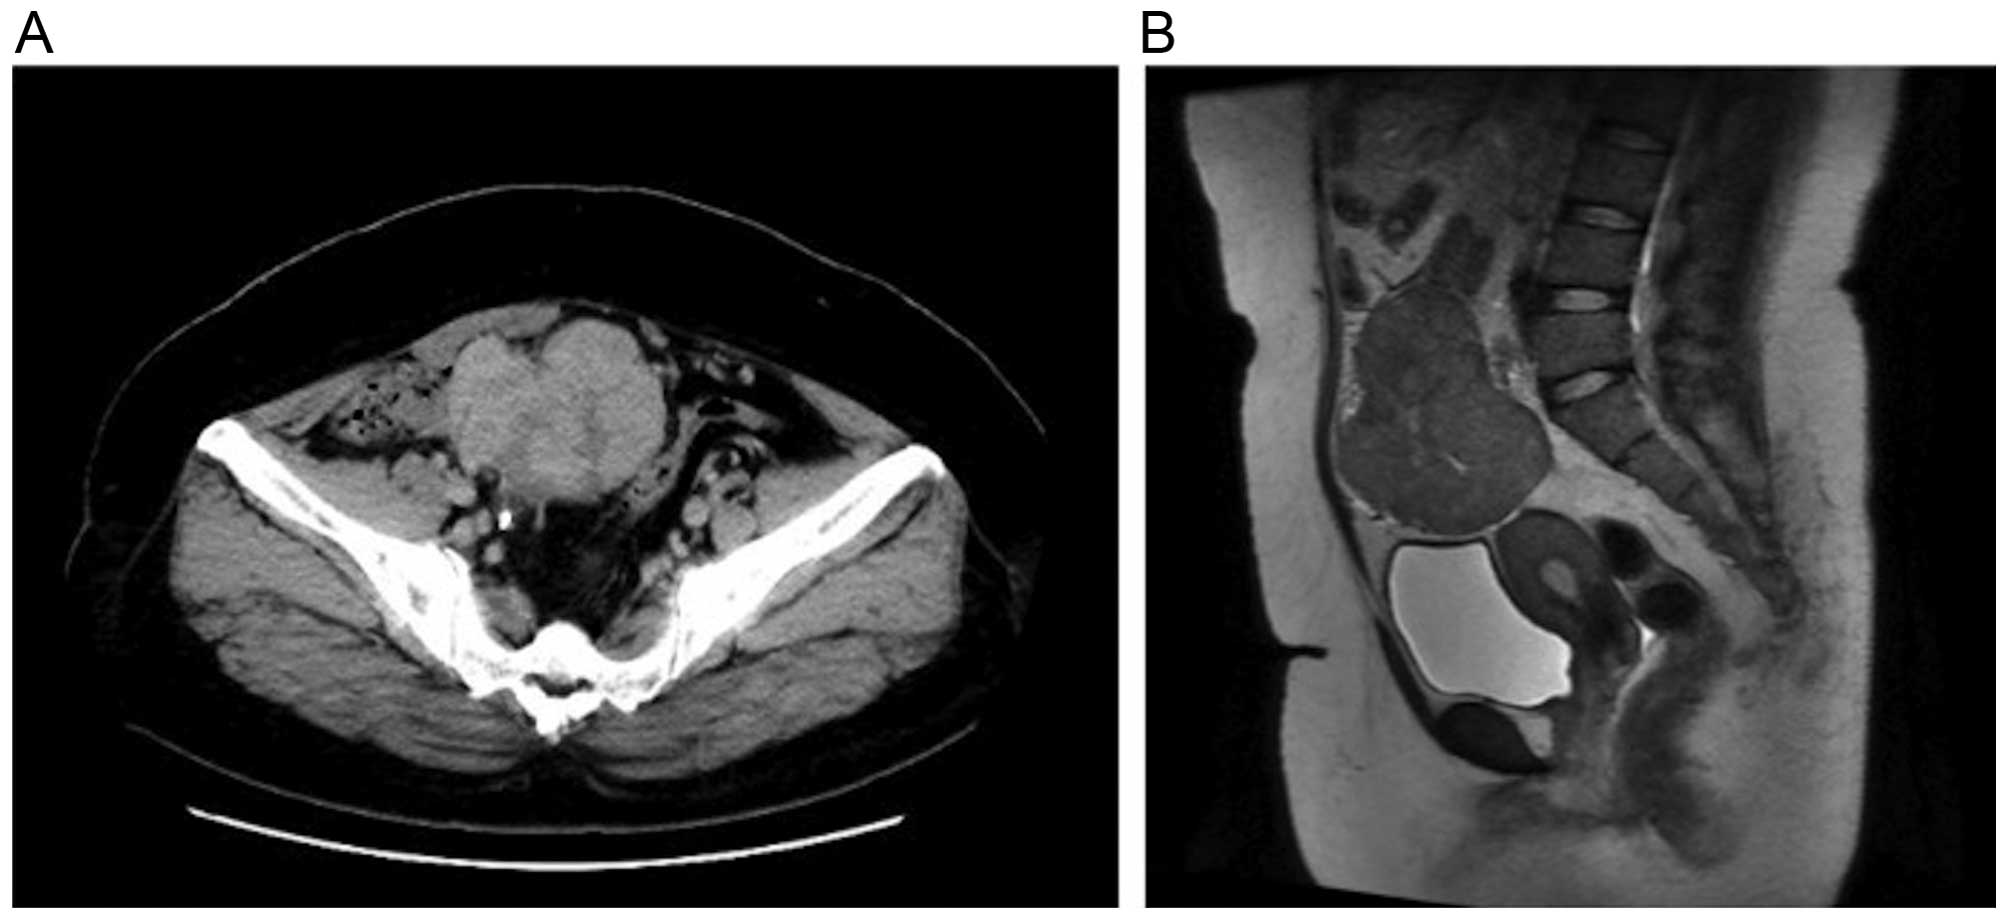

Blood test results upon admission revealed a white blood cell count of 6,100/µl, hemoglobin (Hb) level 10.7 g/dl, platelet count 279,000/µl, aspartate aminotransferase level 21 U/l, alanine aminotransferase level 34 U/l, lactate dehydrogenase 162 U/l, total cholesterol 214 mg/dl, triglycerides 298 mg/dl, BUN 45 mg/dl, Cr 5.4 mg/dl, uric acid 7.3 mg/dl, Na 144 mEq/l, K 4.1 mEq/l, Cl 104 mEq/l, Ca 9.1 mEq/l, blood glucose 101 mg/dl, HbA1c 5.6% and C-reactive protein 2.52 mg/dl. A CT scan revealed a solid mass with a long axis of ~80 mm in the pelvis. There were signs of hydronephrosis in the right kidney due to ureteral compression by the mass, which was hypothesized to have caused postrenal failure. Placement of a ureteral stent in the right ureter alleviated hydronephrosis; the urinary output and blood pressure were normal. BUN and Cr returned to their previous levels and contrast-enhanced CT was performed. The scan revealed a solid mass with mild contrast enhancement that was heterogeneous (Fig. 1A). A tumor was hypothesized to have originated from the adnexa, so the patient was referred to the Department of Obstetrics and Gynecology. A magnetic resonance imaging scan revealed hypointensity on T1-weighted images and a mixture of mildly hypointense areas with some hyperintensity on T2-weighted images. A solid tumor without a cystic component was identified; thus, recurrence of Wilms' tumor, sex cord-stromal tumor and leiomyosarcoma were considered in the differential diagnosis (Fig. 1B). The levels of tumor markers were as follows: Carbohydrate antigen (CA) 125 10 IU/ml, CA19-9 4 U/ml, carcinoembryonic antigen 0.6 mg/ml, squamous cell carcinoma antigen 1.2 ng/ml, neuron-specific enolase 31.8 ng/ml, human chorionic gonadotropin <1.0 mIU/ml and α-fetoprotein 2.0 ng/ml.

Figure 1.

(A) A computed tomography scan revealed a solid mass with mild contrast enhancement that was heterogeneous. (B) A magnetic resonance imaging scan revealed a mixture of mildly hypointense areas with some hyperintensity on T2-weighted images.